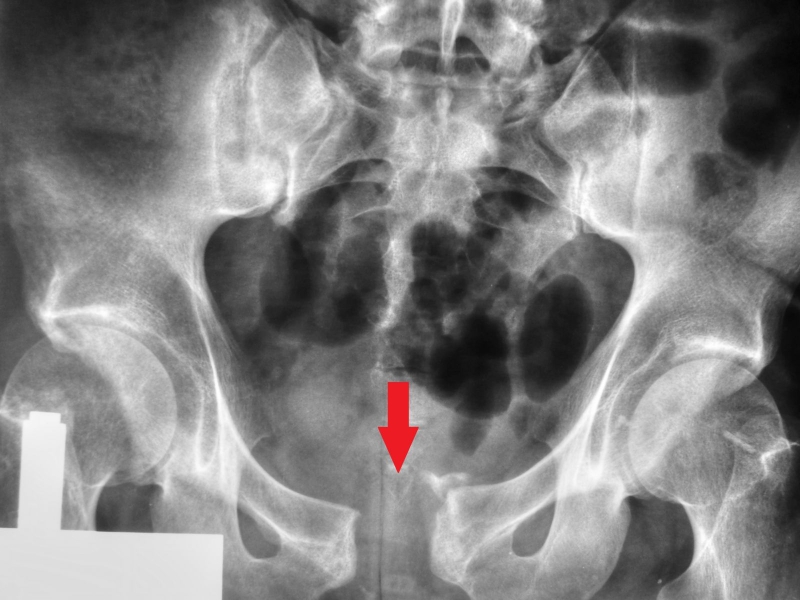

Gãy xương chậu hông có thể chia thành hai trường hợp: Gãy từng phần xương chậu và gãy khung chậu. Gãy khung chậu chiếm tỷ lệ tương đối thấp, chỉ từ 1 - 3% tổng số các trường hợp gãy xương. Tuy nhiên đây lại là những tổn thương nặng nề, phức tạp và có tỷ lệ tử vong cao thứ hai chỉ sau nguyên nhân chấn thương sọ não. Điều trị gãy khung chậu bao gồm điều trị bảo tồn, điều trị kết xương bên trong, điều trị bằng khung cố định ngoài,...

Tình trạng gãy ổ cối

Gãy xương vùng chậu còn có thể được phân loại theo kiểu gãy xương “ổn định” (stable) hoặc “không ổn định” (unstable). Dựa vào mức độ toàn vẹn của cấu trúc vùng chậu sau khi xảy ra chấn thương.